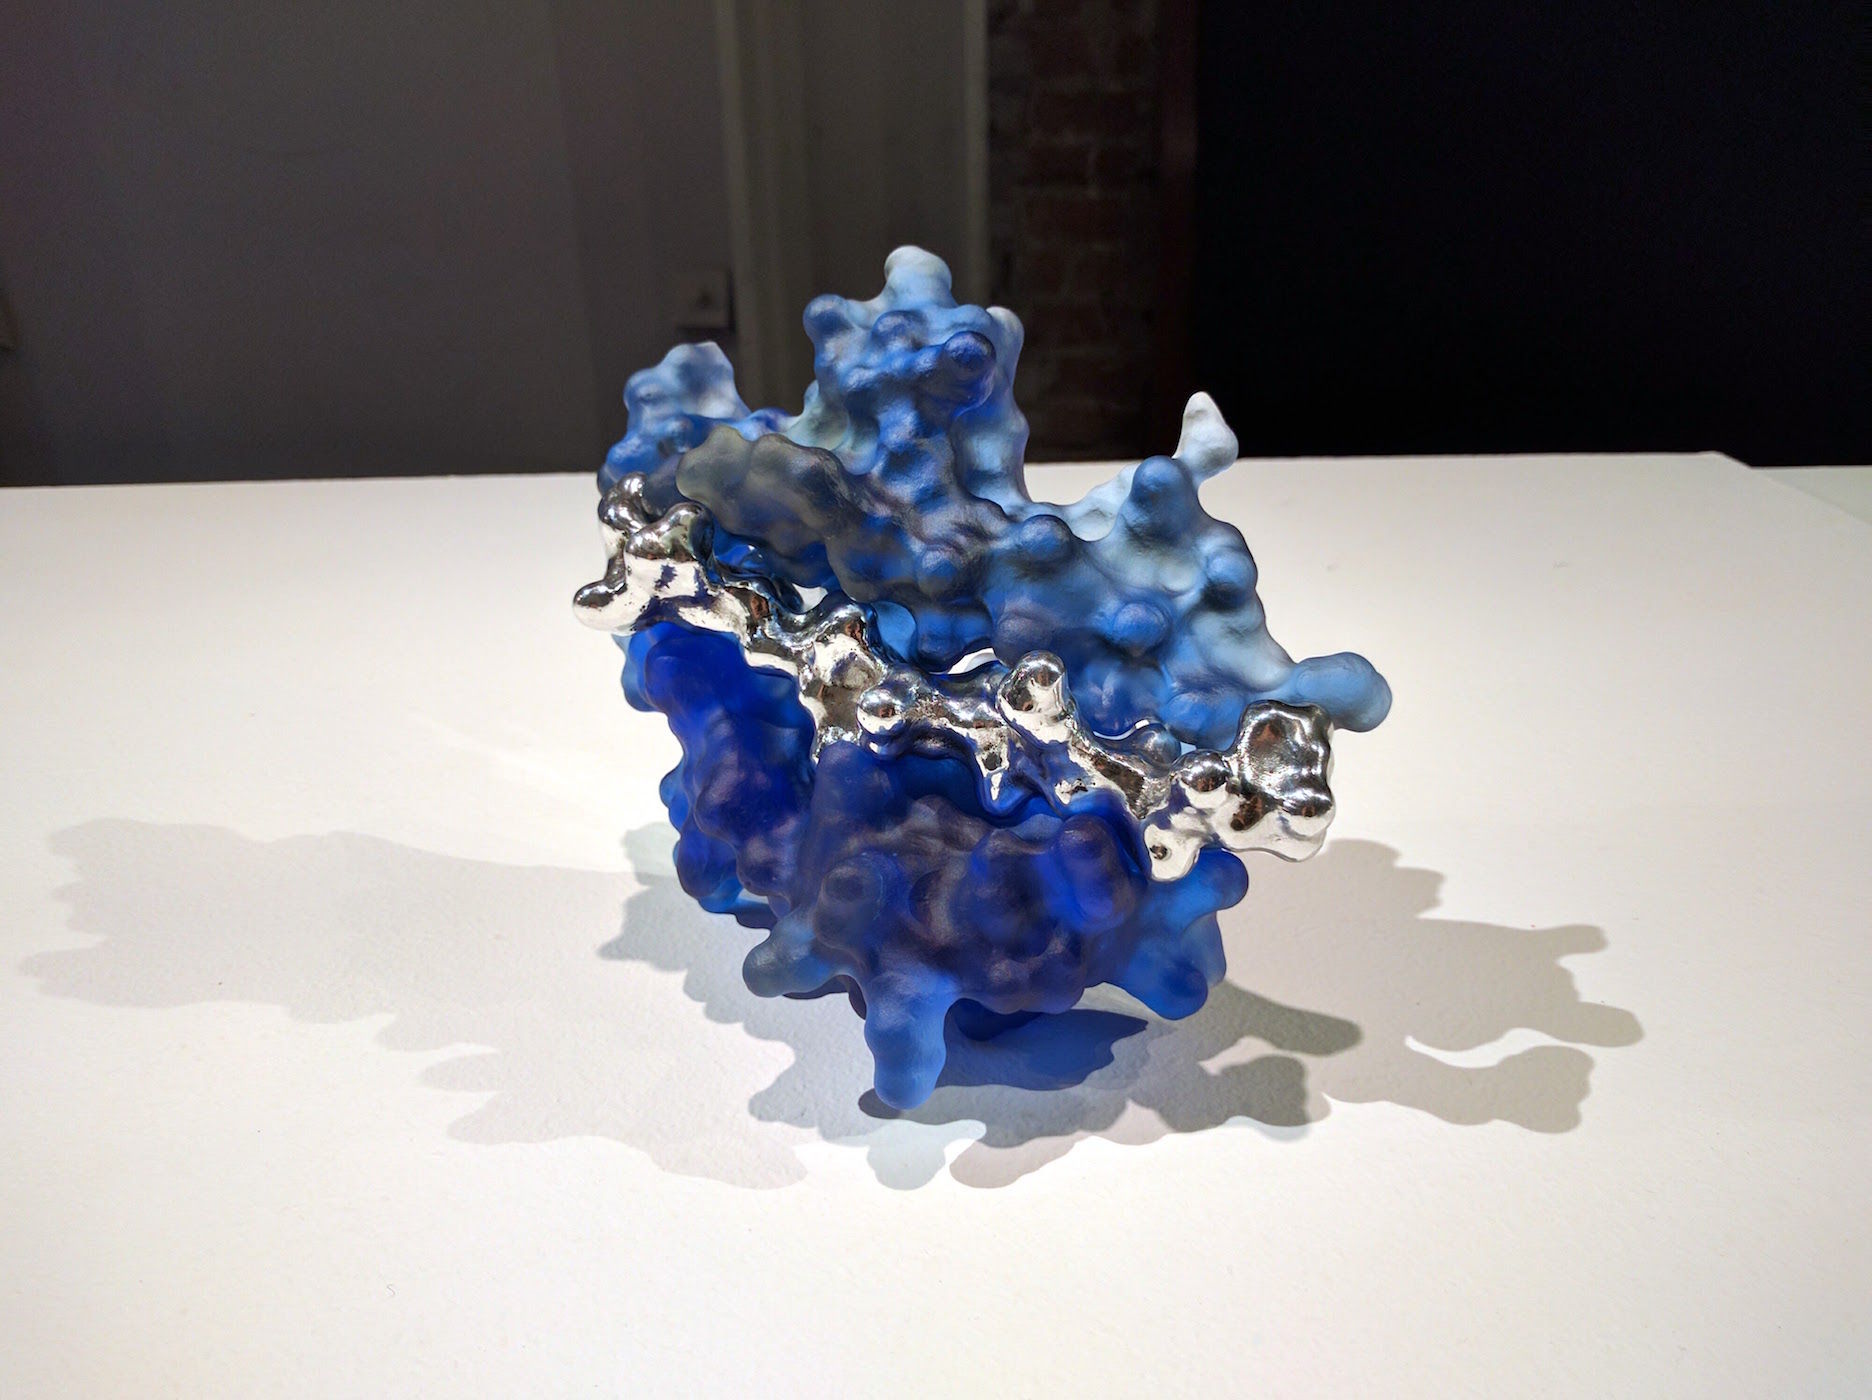

"Tears" - Lysozyme with carbohydrate

Cast bronze, Cast Glass, Wood - 20"x10"x12"

2015

Tears display antibacterial activity, a property that was discovered by Alexander Fleming around the turn of the last century. The active agent, Lysozyme, is also found in saliva, nasal mucus and even breast milk and constitutes a major element in the body's innate immune defense.

Lysozyme was also one of the first proteins and the very first enzyme to have its three dimensional structure elucidated in the 60s through painstaking X-ray crystallography work by David Phillips. The coordinates obtained were used here to create the initial 3D model of the protein which was then 3D printed in plastic, post processed and then recast in clear lead glass using direct lost-PLA casting.

Many bacteria implicated in human disease have a protective cell wall. Lysozyme is an enzyme which digests these carbohydrate barriers, thereby significantly weakening the potential intruders. The carbohydrate, part of which is cast here in bronze, fits tightly into the active site cleft of the Lysozyme enzyme. Deep inside that cleft the cleavage reaction takes place, catalysed by the protein. After cleavage Lysozyme releases both parts and moves on to a new cleavage site, gradually breaking down the cell wall. Discovery of the atom structure led to the first detailed enzymatic mechanism to be described and was a major breakthrough in our understanding of how our bodies' metabolic functions.